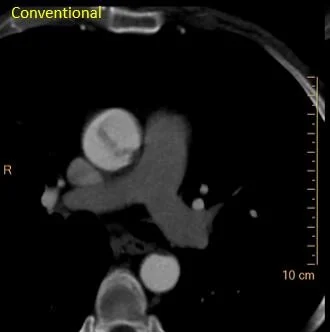

Here is another hypodensity. UA was clean. So these are most likely infarcts.

CT 2 weeks later: Do you see the spleen hypodensity?